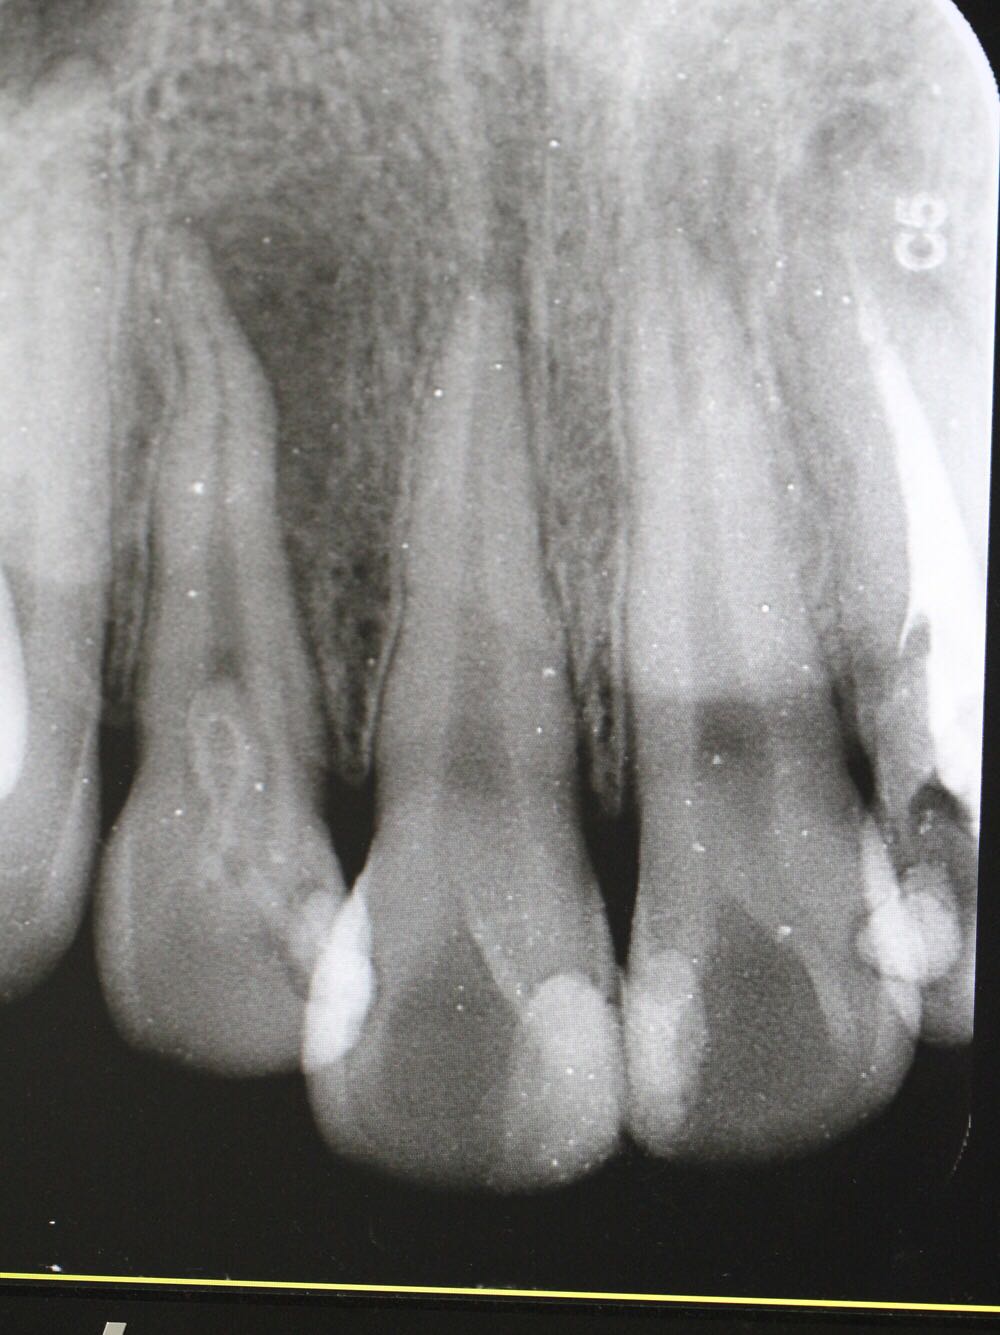

检查:12牙未见明显龋坏,探(-),冷(-),叩(++),无明显松动,牙髓电活力测试无反应,唇侧牙槽粘膜处未见窦道。 X线片:12牙根尖周暗影?

诊断:12牙牙髓坏死? 治疗方案: 1、12牙根管治疗+充填治疗+冠修复 2、12牙择期治疗 3、12牙显微根尖外科手术 4、12牙拔除 5、12牙观察 治疗计划:与患者交流沟通并详细介绍每种治疗方案、费用、时间、预后等,由于患牙根尖病变范围较大,预后欠佳。患者知情、同意并选择方案2,签署知情同意书。 12牙涡轮机开髓,探查根管口,10#,15#K锉疏通根管,根长测量仪测量根管长度,12牙22.5mm,髓腔和根管内放置根管润滑剂,S3扩锉至2506,拍片试尖,X线片示主尖合适。次氯酸啊冲洗根管,P5荡洗,纸尖干燥根管,置氢氧化钙,Caviton暂封。

处置:12牙去暂封,去棉球,根管及髓腔消毒并再次测量并确定根管长度,干燥后,显微镜下使用根尖孔生物材料加大锥度牙胶尖及热牙胶行根尖屏障封闭成形及根管充填,再拍X线片检查根充效果,X线片示根充良好,窝洞消毒,暂封。 医嘱:不适随诊,勿用患牙进食

侧切牙是畸形舌侧沟的好发牙位 釉质发生卷曲 一定程度后 可以形成牙中牙 该部位容易形成细菌通道造成根周的感染 治疗效果欠佳 在完善根管治疗后 应长期随访 必要时行外科手术 如果仍不能有效控制感染 则考虑拔牙